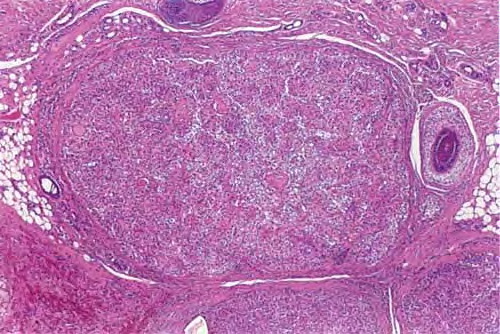

Nodular hidradenoma =الغدوم العرقي العقيدي